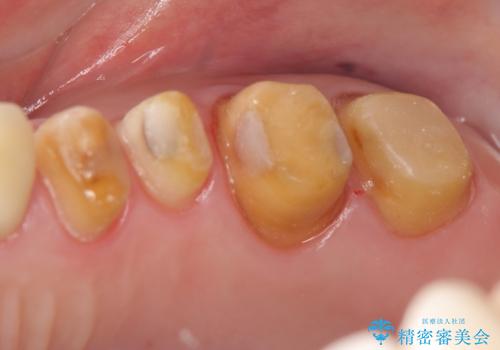

奥歯の被せ物のやり直し 精密根管治療

- 左上の一番奥の歯の根の治療を行いつつ、手前の歯の被せ物のやり直しも一緒に行いました。

手前の被せ物は、メタルボンドクラウンだったため、歯ぐきとの境目が黒くなっていたためやり直しを行いました。

オールジルコニアクラウンに変え、審美的な被せ物になりました。